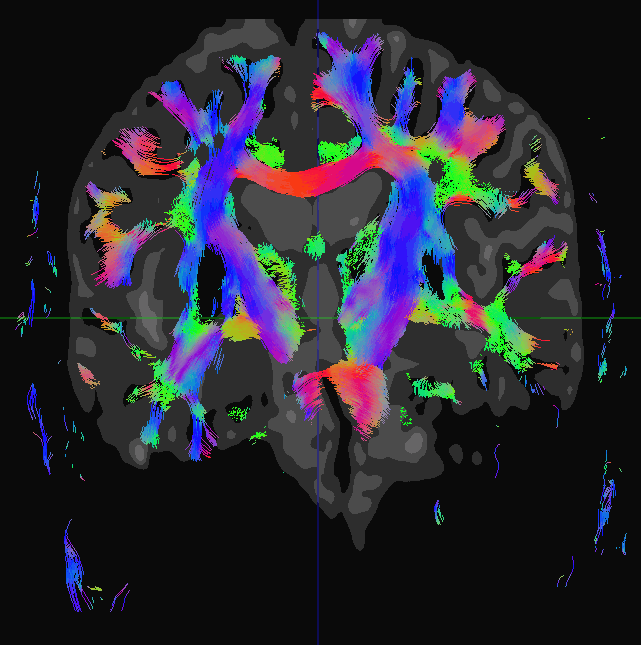

The DICOM Viewer in the MPR reconstruction and Volume reconstruction tabs allows you to show the result of the fiber tractography for the series of Diffusion MRI. Fig. 5.29 shows tracks which are the result of brain tractography.

The tracks which are the result of tractography are refered to as fibers in the DICOM Viewer interface and in the User Manual.